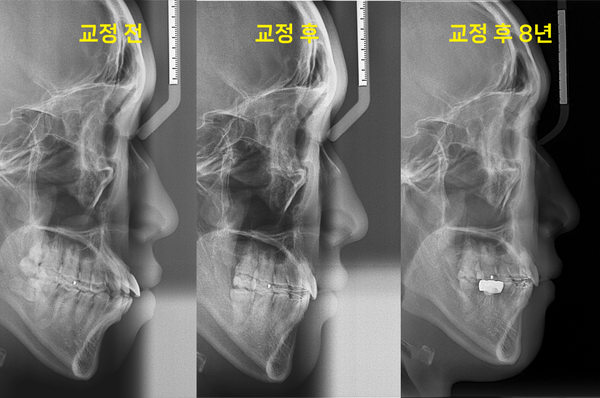

따라서 턱끝이 길면서 무턱이 된 건데요. 무턱과 입술의 돌출감을 개선하기 위해 발치 후 공간을 만들고 상하악 전치를 후방으로 이동과 동시에 수직적인 어금니 조절을 통해 하악골을 반시계방향으로 회전시켰습니다. 하악골이 반시계방향으로 돌아가면 얼굴 길이가 짧아보일 수 있습니다.

이후 환자분의 경우 안모변화가 정말 많이 달라졌는데요. 치료가 끝난 후 8년까지 유지한 상태였습니다.